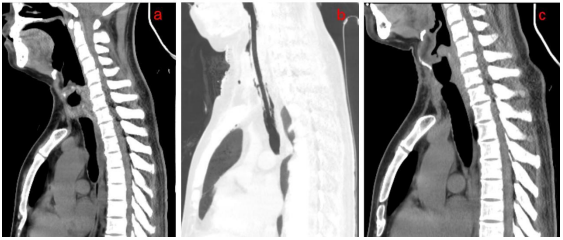

Immediate chest CT and three-dimensional reconstruction of the trachea revealed significant tracheal stenosis (below the cricoid cartilage), with no apparent abnormalities in the rest of the trachea(Figure2 a). Abdominal CT showed resolution of exudative lesions in the abdominal cavity, decreased ascites, and improvement in mesenteric edema. The patient was transferred to the ICU because of confusion consciousness gradually improved, and oxygen saturation increased following sputum aspiration, high-flow noninvasive mechanical ventilation, and oxygen therapy.

Following the surgical procedure, the patient was admitted to the ICU for ongoing treatment while still intubated. The following day, the patient regained full consciousness and was able to breathe spontaneously without any shortness of breath, asthma, or surgical complications(Figure2 b). Subsequent examination using an electronic bronchoscope revealed that the patient’s airway was unobstructed, and no significant narrowing was observed. Following extubation, the patient did not experience any discomfort such as difficulty in breathing.

During a follow-up examination conducted 5 months after the surgery, no new narrowing of the airway was detected, and there was a significant improvement in tracheal stenosis compared to the preoperative condition (Figure2 c).

Figure 2. (a)A CT examination on admission revealed significant narrowing of the trachea (below cricoid cartilage level). (b)A post-operative CT examination revealed that the trachea was intubated, the extent of tracheal stenosis was reduced compared to before, and there was new edema and drainage tube shadowing in the soft tissue of the anterior neck. (c)A CT examination 5 months after surgery showed that the trachea (level below the cricoid cartilage) was slightly narrow, which was significantly better than before surgery, and the edema of the anterior cervical soft tissue subsided